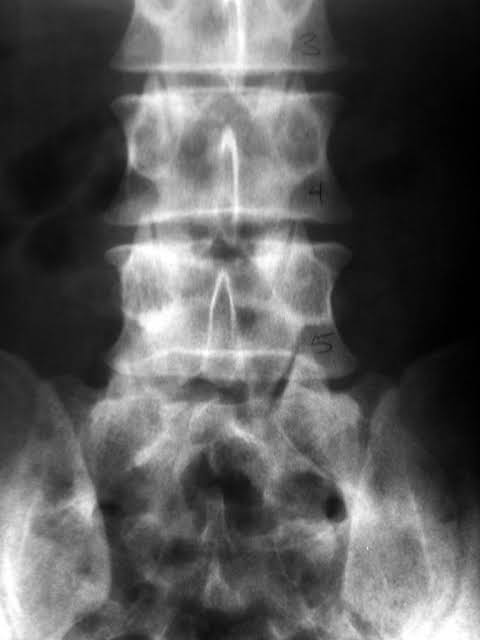

Our back is like the way we build houses.Block/cement/block/cement.

There are 5 bones in the lower back with 5 shock absorbers.

A Doctor’s job is to take a good history and do a full clinical examination. Thereafter, he can order blood tests,xrays,ct scan or an MRI scan to determine what is wrong,where, and plan what to do next.